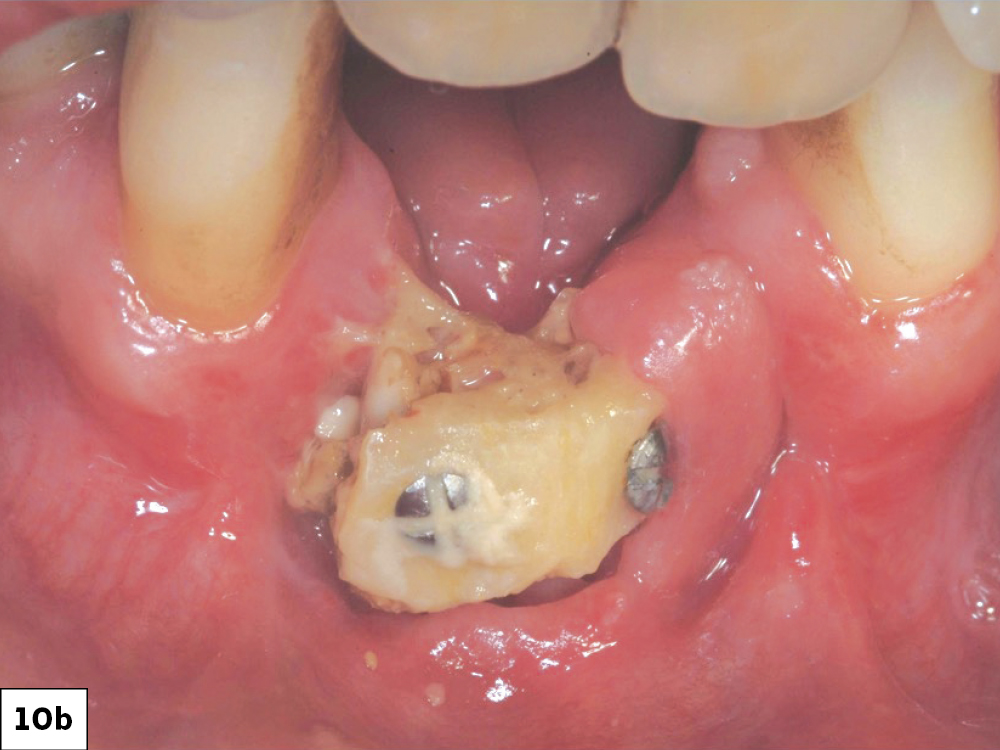

Resuturing wound dehiscences is a challenging procedure, which often results in delayed and unpredictable healing (Fig. 10). Attempting to resuture a fresh wound, particularly when the epithelium is thin and friable, often leads to tearing of the incision line, potentially causing a larger dehiscence or infection. Therefore, resuturing should be approached with care. Greenstein et. al., suggest that resuturing is more viable when the dehiscence is small and occurs within 24 to 48 hours.2 As the wound enlarges (2 to 3 cm) or the time elapsed exceeds 2 to 3 days, the feasibility of excising and resuturing is decreased and commonly results in increased morbidity and should not be attempted.8

Resuturing ILO: (a) Oneweek post-op following bone graft, (b) Twoweek post-op after unsuccessful re-suturing of the surgical wound.

Figures 10a, 10b: Resuturing ILO: (a) One-week post-op following bone graft, (b) Two-week post-op after unsuccessful re-suturing of the surgical wound.